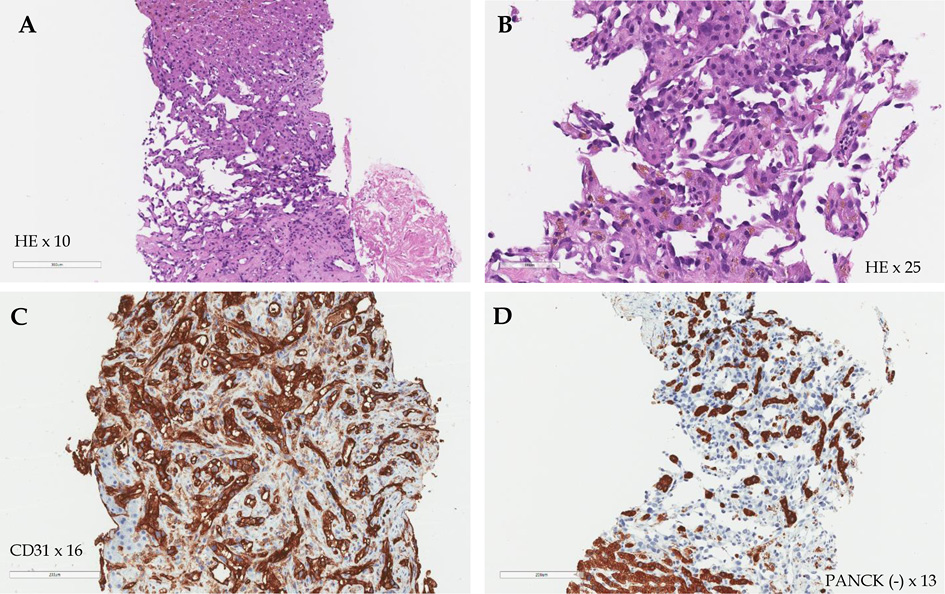

Consequently, a percutaneous focal core needle liver biopsy was performed. The pathological findings confirmed the diagnosis of poorly differentiated (G3) liver angiosarcoma, and the patient was diagnosed with stage IV (cT4N0M1) poorly differentiated (G3) HA with multiple metastases in the spleen and kidneys, severe anemia, and thrombocytopenia. On immunohistochemical examination, the tumor cells showed strong CD31 expression and were negative for CD34, pan Cytokeratin (AE1/AE3) (PANCK) and smooth muscle a-actin (SMA) reactions. Microscopically, the tumor was described as formed by solid, sinusoidal structures of medium caliber cells, featuring eosinophilic cytoplasm (in places with hemosiderin granules) and polymorphic, hyperchromatic nuclei with up to 3 mitoses in the high power field (Figure 3, A–D).

Figure 3. Histological images of the liver. The tumor formed by solid, sinusoidal structures of medium caliber cells, featuring eosinophilic cytoplasm and polymorphic, hyperchromatic nuclei (Hematoxylin-eosin (HE) staining, 10 × and 25 × magnitude) (A, B); strong CD31 expression (CD31 staining, 16 × magnitude) (C); negative PANCK reaction (D).